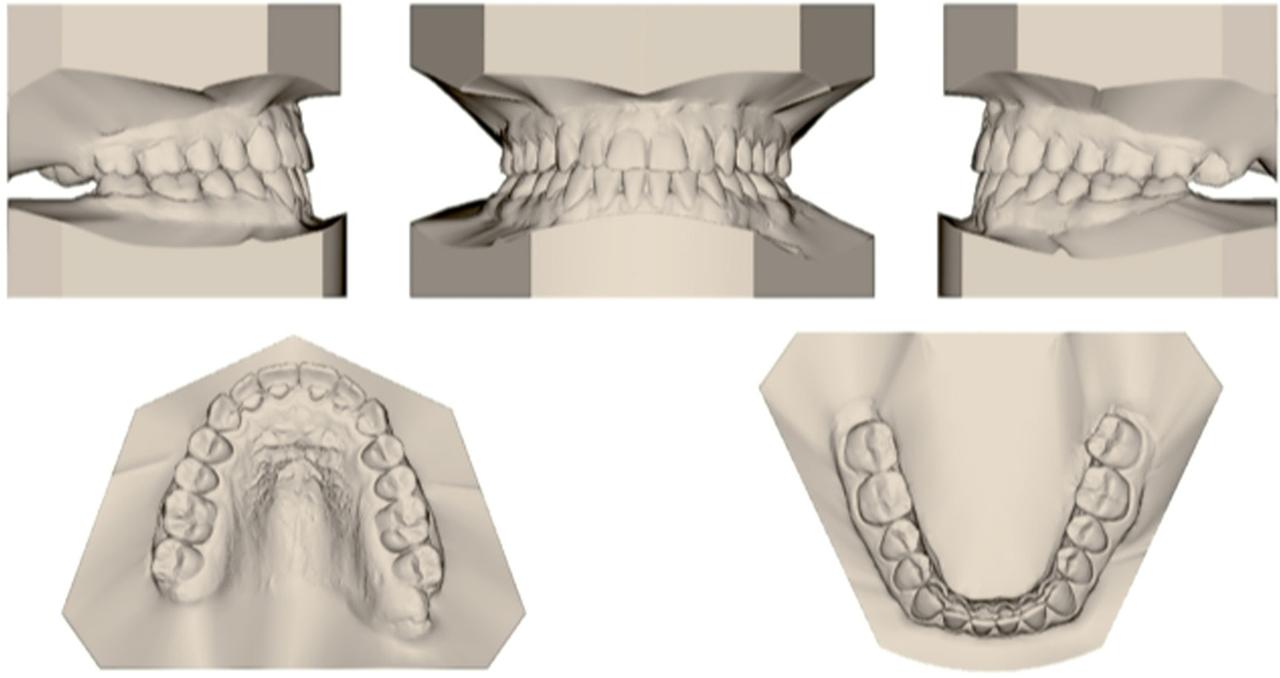

Figure 2

Pre-treatment dental casts.

A 21-year, 8-month-old, female patient presented with the chief complaint of an unaesthetic prominence of her chin. The patient was healthy, practised good oral hygiene, and had no periodontal nor temporomandibular joint problems. She had a Class III molar and canine relationship bilaterally plus a negative overjet (−2.2 mm), along with anterior and bilateral posterior cross-bites. The lower dental midline had slightly shifted to the right. A facial analysis revealed a concave profile, a mild maxillary deficiency and a protrusive lower lip (Fig. 1). According to a dental cast analysis, 1.5 mm of maxillary and 2.5 mm of mandibular crowding were present, in addition to a 1.3 mm lower anterior Bolton excess (Fig. 2).